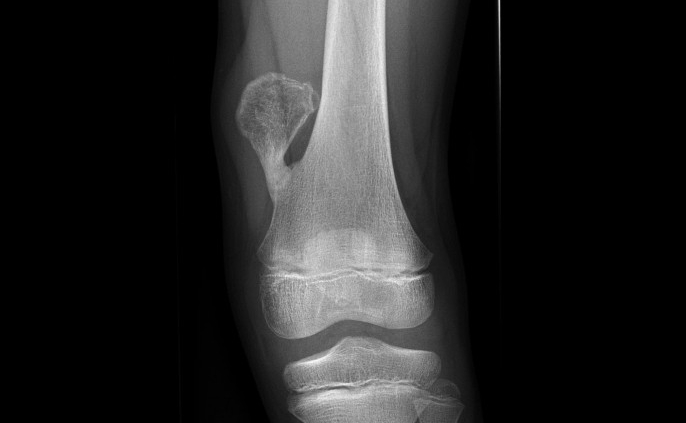

Exostoza apare de obicei în copilărie. Elementele care conduc la diagnosticul clinic al afecţiunii sunt variabile de la un copil la altul. Cel mai adesea se constată o excrescenţă osoasă dură, fixă, situată la nivelul extremităţilor oaselor lungi ale membrelor, la joncţiunea între corpul osului şi extremitatea sa (regiunea metafizară). Cartilajele de creştere ale oaselor lungi, care realizează creşterea în lungime a osului sunt localizate la nivelul acestor regiuni metafizare. Regiunile cele mai afectate sunt cele ale genunchilor, umerilor, gambelor şi pumnului. Coatele, coloana vertebrală, omoplaţii şi bazinul sunt mai rar afectate.

Numărul exostozelor variază amplu de la o persoană la alta şi chiar în cadrul aceleiaşi familii. Dimensiunile exostozelor cresc pe parcursul copilărie, rămânând apoi rămân relativ constante. Sunt posibile deformaţii ale membrelor, în special deformaţia antebraţului şi a pumnului, cu deviaţia spre exterior a mâinii, legată de.o răsucire a cubitusului sau deformaţia gambei (genu valgum). Pot apare şi deformări ale oaselor mâinii şi piciorului.

- excrescenţă osoasă dură, fixă, situată la nivelul extremităţilor oaselor lungi ale membrelor, la joncţiunea între corpul osului şi extremitatea sa (regiunea metafizară);

- sunt posibile deformaţii ale membrelor, în special deformaţia antebraţului şi a pumnului, cu deviaţia spre exterior a mâinii, legată de o răsucire a cubitusului sau deformaţia gambei (genu valgum);

Exostoza este situată in metafiza oaselor lungi.

Exostoza solitară, în peste 50% din cazuri, se localizează în extremitatea inferioară a femurului, superioară a tibiei și.a humerusului, dar uneori poate să apară și pe vertebre, sacru, clavicula, oasele mici ale mâinii și piciorului.

Diagnosticul se stabileşte pe baza examenului clinic, completat de radiografii osoase care nu sunt utilizate decât pentru exostozele localizate în regiuni greu accesibile examenului clinic. Informativitatea tomografiilor sau a investigaţiilor RMN este redusă, la acestea recurgându-se doar în cazul localizărilor vertebrale.

Radiografia osoasă identifică leziunile caracteristice și diformitățile asociate.